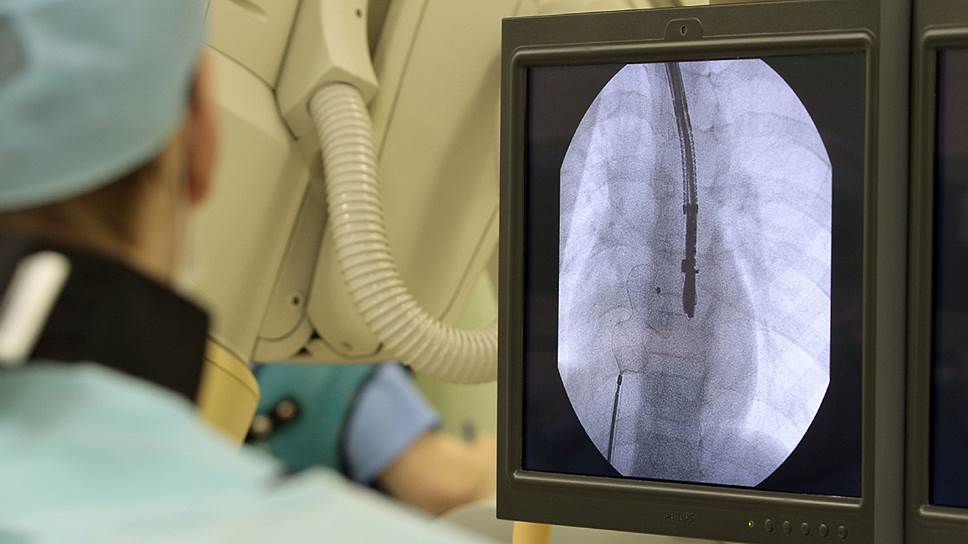

Один из самых тяжелых врожденных пороков сердца — единственный желудочек; без медицинской помощи прогноз для таких младенцев крайне неблагоприятный. Но современная кардиохирургия позволяет им не просто выжить, но и существовать полноценно. Для этого, в частности, производится операция Фонтена: правое предсердие соединяется с легочной артерией и, таким образом, выполняет функцию правого желудочка, а единственный желудочек работает как левый, обеспечивая кровообращение по большому кругу.